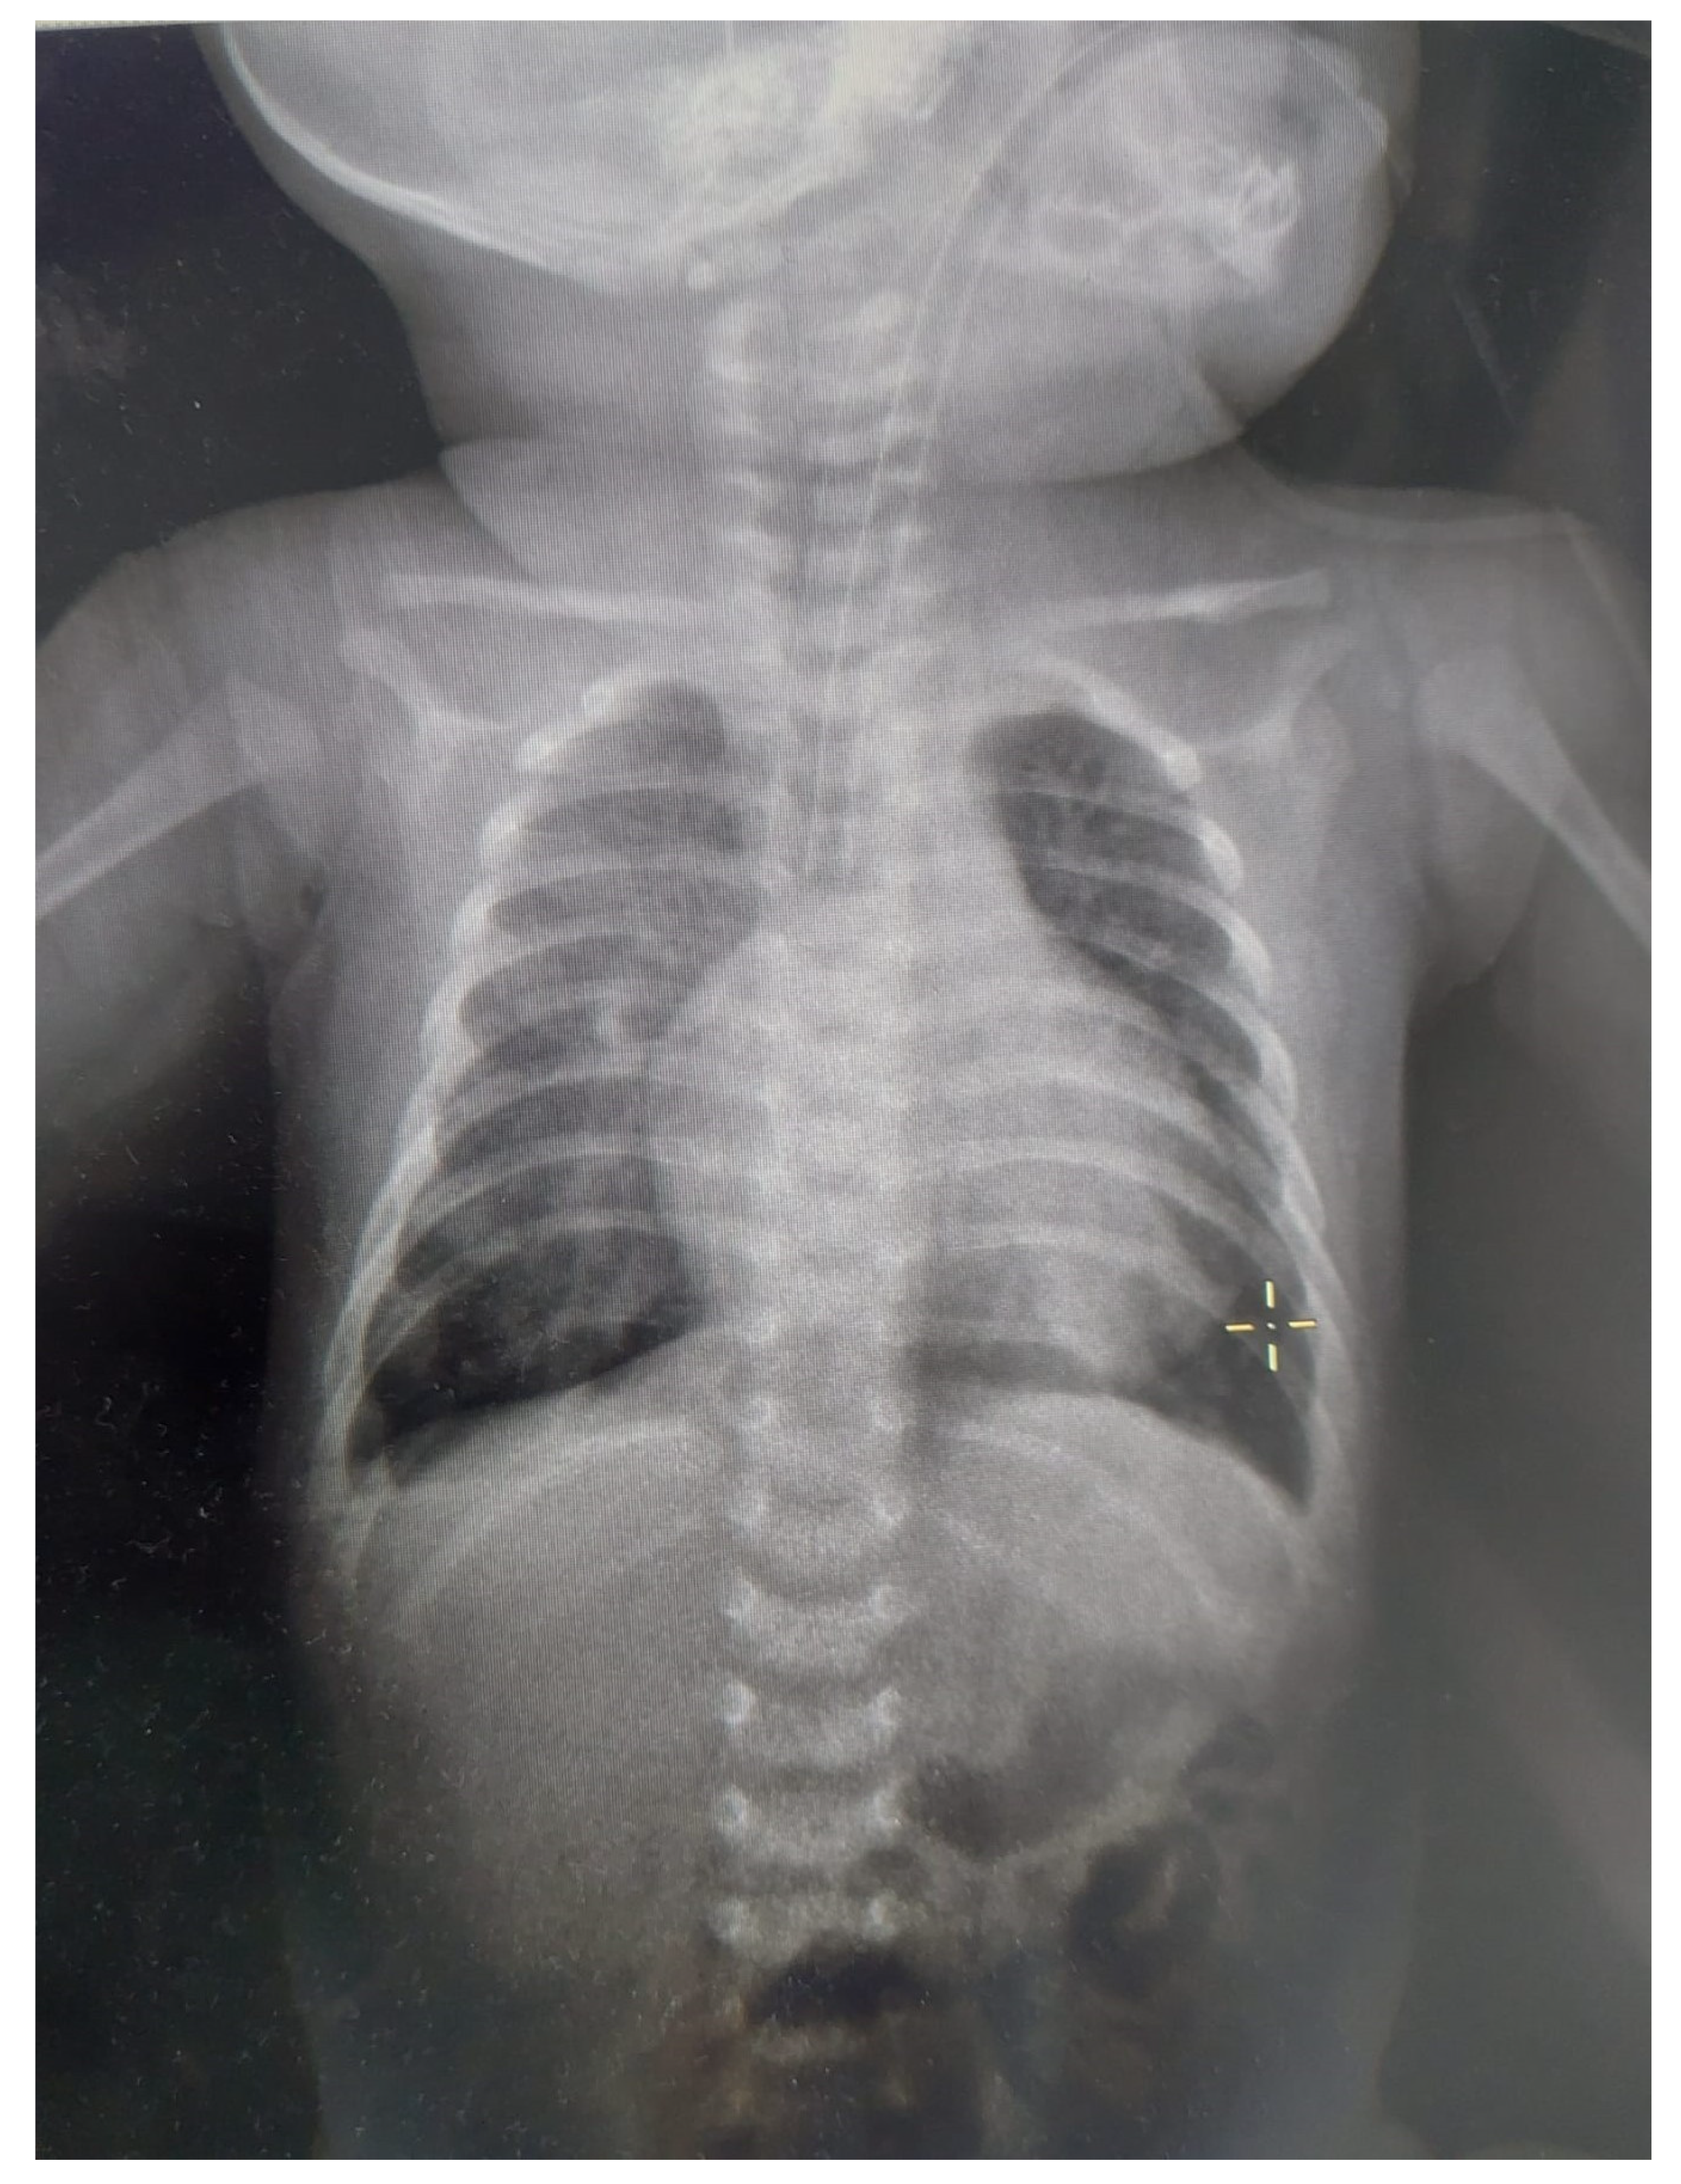

2. Case Report